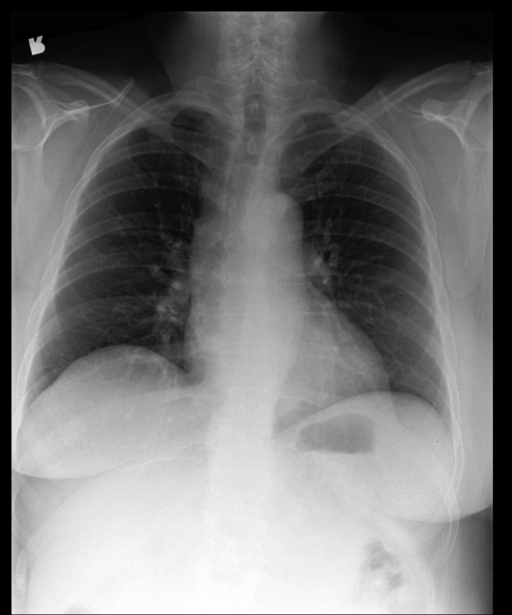

Probs: 0.020, 0.955, 0.922, 0.210, 0.916

Report:

There is elevation of the left hemidiaphragm…

No pleural effusion.

No pneumothorax.

Normal cardiomediastinal silhouette.

There are healed left-sided rib fractures.